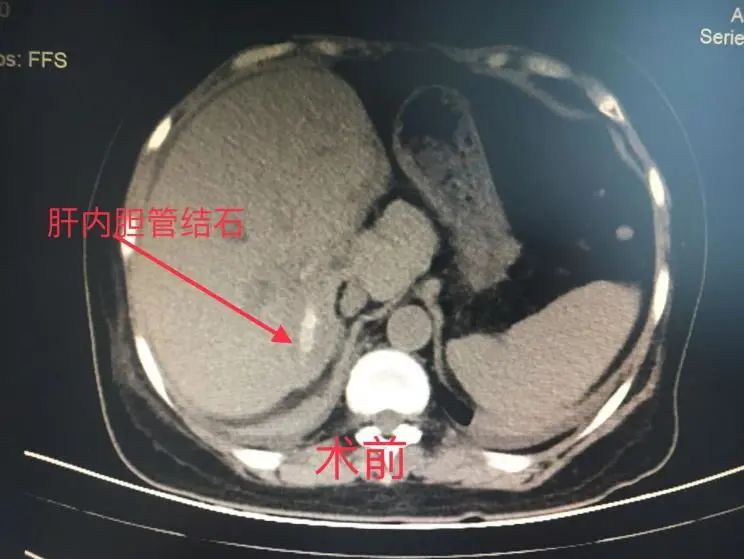

终于患者急性胆管炎再次发作,忍无可忍,经人介绍,患者来到了肝胆外科李金海副主任医师门诊,第一次见到患者看到的是一个极其虚弱的身体:全身皮肤及眼睛发黄,而且发热高达39℃,中上腹痛明显,术前胆红素指标更是高达134umol/L(正常值是0-28umol/L),提示右肝管脱落的结石已经引发胆总管梗阻,引起胆总管的急性梗阻性化脓性炎症。CT看起来患者的右后叶胆管已经有明显的“铸型结石”,按外科的原则,是需要手术治疗的。一双儿女听说母亲的病情,也从外地专门回到瑞安。患者女儿反复说我妈妈这个右肝管结石在北京协和医院手术的专家看了说是没办法祛除的。从患者本人紧锁的眉头看得出来,她对自己的疾病好像也并没有太大信心能治好。